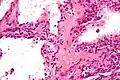

![]() | |

| Micrograph showing a pancreatic serous cystadenoma. H&E stain. | |